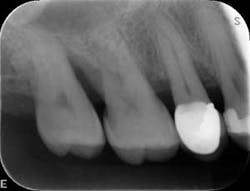

Dental examination revealed gingival swelling and bleeding on probing. Periodontal probing showed moderate-to-deep pocket depths in all posterior teeth (figures 1–3). Generalized bone loss was observed on radiographs (figures 4–6). Tooth vitality and percussion tests were negative. Teeth 2, 3, 31, 14, and 15 had Class III mobility. The patient was diagnosed with Type IV chronic adult periodontitis. Treatment options were discussed, and, after explanation, the patient agreed to the LANAP procedure.

At nine months, the patient’s tissues appeared pink with no inflammation. Radiographs revealed new bone growth, especially around teeth Nos. 3, 15, and 31 (figures 10–12). The patient reported his HbA1c level stable at 8.2.

Patient presentation before LANAP treatment (figures 1–6)

Radiographs nine months after LANAP treatment (figures 10–12)